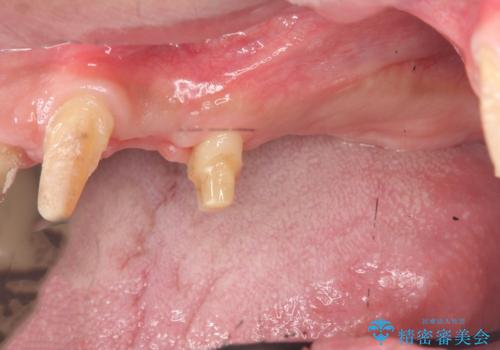

- 「全体的に歯が揺れ、今後の歯の健康に不安がある。歯周病の治療を受けたい。」、と来院されました。

精密検査の結果、重度の歯周病が認められ大きな骨の吸収を認めました。

予後の悪く保存の難しい歯を抜去し、骨の造成を含んだインプラント治療を計画します。